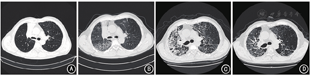

患者男,67岁,因反复咳嗽、咳痰、痰中带血1年余,确诊右上肺小细胞肺癌5个月余,气促1个月,加重1 d,于2021年11月12日收入陆军军医大学西南医院(我院)呼吸与危重症监护病房。5个月前,患者因反复咳嗽、咳痰、痰中带血等至外院就诊,诊断为右上肺小细胞肺癌,给予化疗联合免疫治疗,方案为伊立替康240 mg+奈达铂110 mg+替雷利珠单抗200 mg静脉滴注、第1天,21 d为1个周期。治疗1周后患者咳嗽明显好转,无痰中带血。治疗2个周期后,至我院复查胸部CT示双肺散在结节,较大磨玻璃结节位于右肺下叶背段,大小13 mm×12 mm(图1A)。实验室检查结果示白细胞计数(white blood cell count,WBC)5.7×109/L,血小板计数12×109/L,血红蛋白132 g/L,神经烯醇化酶(neuron-specific enolase,NSE)12.11 μg/L(参考值:<25.00 μg/L)。诊断为Ⅳ度骨髓抑制,暂停化疗和免疫治疗,给予升血小板治疗5 d后血小板计数119×109/L。自2021年8月,患者规律行肺部肿瘤放射治疗(放疗),2个月后出现阵发性咳嗽、咳痰,痰中带血丝,鲜红色,量不多,伴气促(咳嗽时明显),无发热,患者自行口服复方甘草口服溶液无明显缓解。实验室检查示WBC 6.2×109/L,NSE 15.96 μg/L;胸部CT复查示双肺结节等陈旧性病灶较前变化不大,新增双肺网格状模糊影,以右肺为甚(图1B)。考虑为双肺间质性肺炎,停止放疗,予扩张气道、祛痰、止血等对症治疗,并重启化疗(伊立替康+洛铂)。之后患者仍间断咳嗽、咳痰,咳白色泡沫痰,痰中带血逐渐停止,气促逐渐加重。遂至门诊复查,血气分析(未吸氧)示pH 7.47、二氧化碳分压(partial pressure of carbon dioxide,PCO2)30 mmHg(1 mmHg=0.133 kPa)、氧分压(partial pressure of oxygen,PO2)32 mmHg、乳酸1.60 mmol/L,诊断为Ⅰ型呼吸衰竭,收入院。患者既往无糖尿病、高血压病等慢性病史,直肠息肉切除术后5年。家族史无特殊。吸烟史40年(20支/d),已戒烟1年;偶饮白酒(3两/次)。无药物及食物过敏史。

入院体检:体温39.7 ℃,脉搏111次/min,呼吸31次/min,血压95/51 mmHg。痛苦面容,唇及双手双脚重度紫绀,皮温高,呼吸急促,右上肺语颤较左侧减弱,右上肺叩诊稍浊。双肺呼吸音粗,双肺未闻及干湿性啰音。实验室检查:WBC 6.3×109/L,中性粒细胞0.77,红细胞计数2.85×1012/L,血红蛋白86 g/L,血小板计数322×109/L,C反应蛋白131 mg/L,降钙素原0.75 μg/L,红细胞沉降率84 mm/1 h,N末端脑钠肽前体1 101 ng/L,NSE 19.3 μg/L。胸部CT检查:双肺结节等陈旧病灶较前变化不大,双肺网格状模糊影、右肺及左肺上叶间质性改变较前明显加重(图1C)。血气分析(未吸氧)示pH 7.46,PCO2 30 mmHg,PO2 34 mmHg,血氧饱和度0.70,氧合指数161。入院诊断:右上肺小细胞肺癌(T2N2M0 Ⅲa期,局限期)左肺门、纵膈淋巴结转移,双肺间质性肺炎,重度Ⅰ型呼吸衰竭。结合患者用药史,考虑为免疫相关性肺炎合并感染可能性大。入院当天给予注射用甲泼尼龙琥珀酸钠(甲泼尼龙)80 mg静脉滴注、3次/d,美罗培南1 g静脉滴注、3次/d,辅以吸氧(吸氧浓度50%)和物理降温等治疗。第2天,患者体温恢复正常,轻微咳嗽,明显气促;血气分析(吸氧浓度50%)示pH 7.43,PCO2 34 mmHg,PO2 65 mmHg,血氧饱和度0.93,氧合指数130;G试验(-)。因G试验不能检测接合菌纲和隐球菌,且可能出现假阴性,仍考虑免疫相关性肺炎合并感染,真菌暂不除外,加用丙种球蛋白25 g静脉滴注、1次/d;患者氧合指数差,病情危重,加用莫西沙星0.4 g静脉滴注、1次/d和氟康唑0.2 g静脉滴注、1次/d。入院第4天,患者偶有轻微咳嗽,气促明显。血气分析(吸氧浓度50%)示pH 7.50,PCO2 33 mmHg,PO2 72 mmHg,血氧饱和度0.96,氧合指数144,GM试验(-);11项呼吸道病原体(肺炎支原体、肺炎衣原体、嗜肺军团菌、柯萨奇病毒A型、柯萨奇病毒B型、埃可病毒、甲型流感病毒、乙型流感病毒、呼吸道合胞病毒、腺病毒、副流感病毒)血清免疫球蛋白M均阴性。床旁胸部X线检查示右肺内片状高密度影,左肺散在密度增高影。考虑双肺炎症较前变化不大,感染不能排除。将甲泼尼龙剂量减少至40 mg静脉滴注、3次/d,氟康唑调整为伏立康唑0.2 g静脉滴注、2次/d。第6天,患者气促好转,实验室检查示WBC 12.0×109/L、中性粒细胞0.91、C反应蛋白15.5 mg/L;血气分析(吸氧浓度50%)示pH 7.47,PCO2 37 mmHg,PO2 74 mmHg,血氧饱和度0.96,氧合指数148;GM试验(+),血细菌、真菌培养及痰细菌培养均为阴性。加用英夫利昔单抗300 mg静脉滴注、1次/2周。第7天,患者气促明显好转,床旁胸部X线检查提示双肺炎症减轻,调整甲泼尼龙剂量为60 mg静脉滴注、2次/d,停用丙种球蛋白。第13天,患者气促进一步好转,实验室检查示WBC 11.9×109/L,中性粒细胞0.93,C反应蛋白1.01 mg/L,降钙素原0.12 μg/L;血气分析(吸氧浓度28%)示pH 7.49,PCO2 39 mmHg,PO2 67 mmHg,血氧饱和度0.96,氧合指数203;痰真菌培养阴性;胸部X线检查提示右肺炎症进一步减轻。将甲泼尼龙剂量减少至40 mg静脉滴注、2次/d。第15天,伏立康唑血药浓度为0.42 g/L(参考值:0.50~ 5.00 g/L),将伏立康唑剂量增加为0.3 g静脉滴注、2次/d。第17天,复查胸部CT提示右肺炎症部分吸收,部分肺组织复张;血气分析(吸氧浓度28%)示:pH 7.48,PCO2 35 mmHg,PO2 69 mmHg,血氧饱和度0.96,氧合指数246。停用美罗培南。第20天,患者未诉不适,实验室检查示WBC 15.5×109/L、中性粒细胞0.91、降钙素原0.11μg/L,予英夫利昔单抗300 mg(总第2剂)。第23天,血气分析(吸氧浓度41%)示pH 7.47,PCO2 35 mmHg,PO2 69 mmHg,血氧饱和度0.95,氧合指数246;将甲泼尼龙调至60 mg静脉滴注、1次/d。第32天,实验室检查示WBC 9.3×109/L、中性粒细胞0.85、C反应蛋白1.49 mg/L,胸部CT复查示双肺结节等陈旧性病灶较前变化不大,双肺间质性改变范围较前缩小(图1D)。第34天,患者无咳嗽、咳痰、气促,口唇及双手双脚轻度紫绀,血气分析(吸氧浓度29%)示pH 7.49,PCO2 35 mmHg,PO2 64 mmHg,血氧饱和度0.94,氧合指数220,病情稳定,出院。嘱患者口服甲泼尼龙片48 mg、1次/d,逐渐减量至停用。